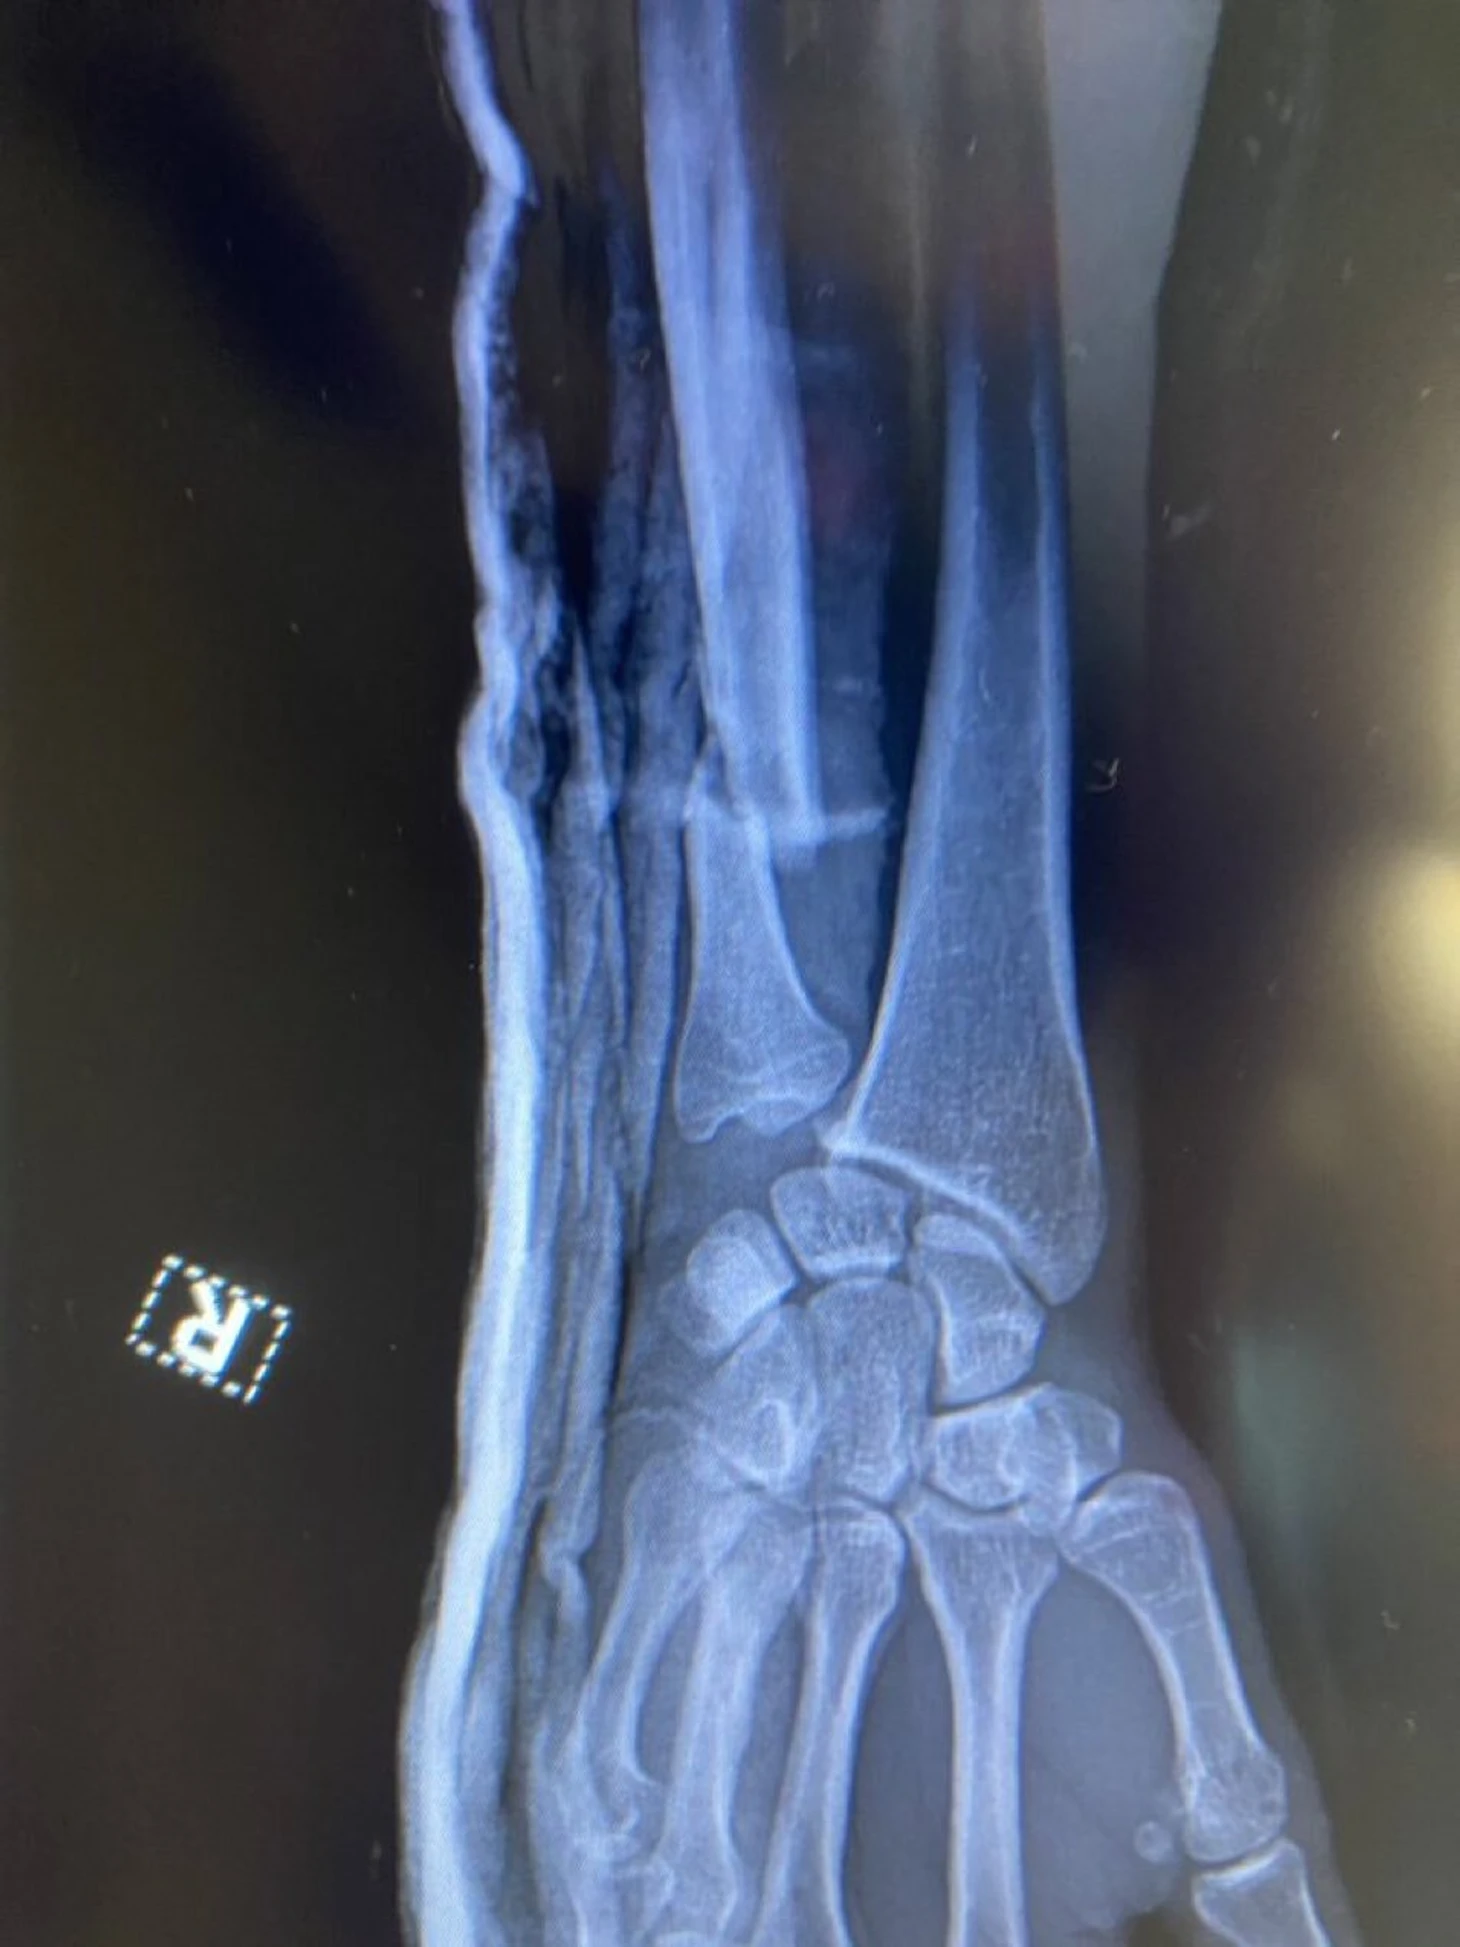

Дэн Хукер показал рентген руки после победы над Тернером – перелом

Боец UFC Дэн Хукер сломал руку в поединке с Джалином Тернером.

Спортсмен показал рентгеновский снимок руки – перелом.